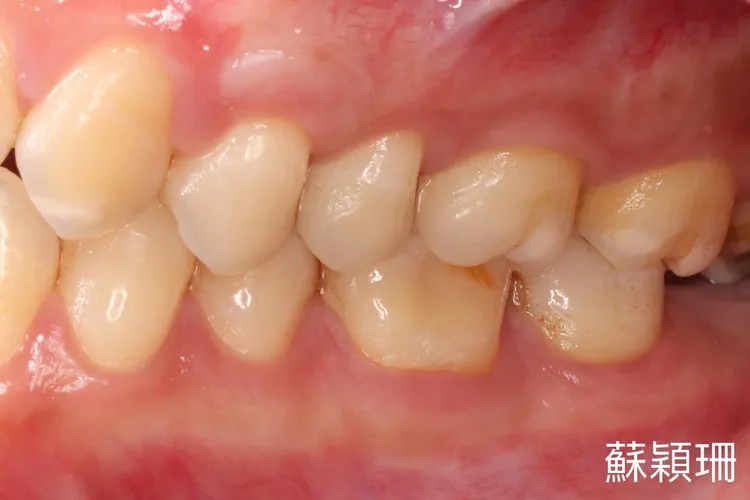

台北慈濟院牙科醫師蘇穎珊說明,正常牙齦的高度應位於牙釉質、牙骨質的交界處,牙齦除了會著年齡大而退縮。不當的牙刷與刷牙方式、刷牙用力過度、天生牙齒結構問題如邊緣軟組織較薄、高位繫帶、牙齒錯位、牙根外突或牙周炎、矯正治療及牙周治療後的副作用也都有可能出現牙齦退縮情況。

台灣研究指出,30 歲以下的人,有31%的人可以觀察到牙齦退縮的現象,然而年齡大於30歲以上的人,則有大於80%的人有牙齦退縮。

治療牙齦退縮的手術方法眾多,包括蒂狀瓣移植、皮下結締組織移植、游離牙齦移植、引導組織再生手術、牙釉基質衍生物治療等。但蘇穎珊提醒,不管哪一種手術,都會因為患者本身的口腔衛生習慣以及牙齒本身結構等而有約10~40%的復發率。

許多人為了要將牙齒刷乾淨而暴力刷牙,或選用粗硬刷毛的牙刷,卻導致牙齦創傷。蘇穎珊提醒,刷牙宜採改良式貝氏刷牙法和軟毛牙刷,民眾要規律作口腔檢查,如有牙齦退縮的情況,應讓牙周病專科醫師鑑別退縮原因、嚴重程度以及時治療。